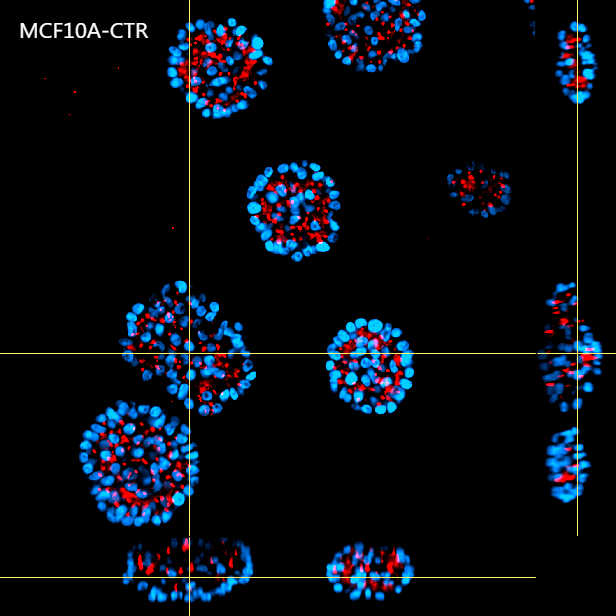

Figure 4 shows a maximum intensity projection (MIP) of 60 um Z-stack of non-malignant (A) and tumorigenic (B) acini. By providing homogeneous illumination over the entire 25 mm field of view (FOV), the X-Light V3 confocal spinning disk allowed us to analyze a large number of acini, reducing the number of images required to obtain robust data and, therefore, minimizing acquisition time.

A

B

Figure 4: MIP from 60 um Z-stack of non-malignant (A) and tumorigenic acini (B). Cells were cultured in 3D Matrigel suspensions and stained with pericentrin (red) and DAPI (blue). These images were acquired with a CFI Plan Apochromat Lambda D 20x air objective (20x, Nikon, 0.8 NA and 0.8 mm WD).

Using such an automated analysis pipeline, we have collected a wide range of information useful in understanding how mutated Ras receptors affect the proliferation and morphology of acini. As shown in Figure 8A, acinar structures from cultures of non-malignant breast cancer typically have round symmetrical shapes. On the other hand, the acini from malignant breast cancer cultures cause a deformation in the 3D architecture which causes the shape of the acini to be more elongated and deconstructed. Notably, the spheroids derived from the MCF10A K-Ras engineered line has a significant volume increase compared to the control line (Figure 8B). In fact, the transforming contribution of the k-Ras oncogene correlates with the increase in the cellular proliferative rate, and this causes an increase in volume already after 6 days in culture.

A

B

Figure 8: Representative MCF10A-CTR and MCF10A-RAS acini (A) and volume analysis (um3) (B). Cells were cultured in 3D Matrigel suspensions and stained with pericentrin (red) and DAPI (blue). This image was acquired with a CFI Plan Apochromat Lambda D 20x air objective (20x, Nikon, 0.8 NA and 0.8 mm WD). Volume comparison between MCF10A-CTR and MCF10A-RAS acini (B).